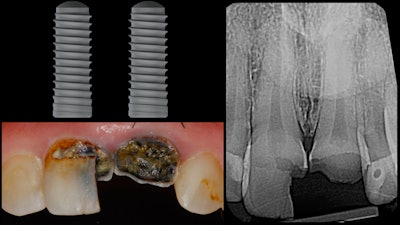

This patient presented with severe coronal caries for teeth #8 and #9. Anticipating both teeth to be nonrestorable, a treatment plan for two implants was developed (figure 1). Before treatment, the patient's intraoral condition was imaged using the Cerec Omnicam (Dentsply Sirona). A CBCT image was obtained using the Orthophos XG 3D.

We merged the patient's two datasets (teeth and soft tissue and also osseous information) using implant treatment planning software. From this we developed a prosthetically driven virtual surgical plan. At that point, we also designed a surgical guide that was 3D-printed in advance of the implant placement surgery (figure 2).